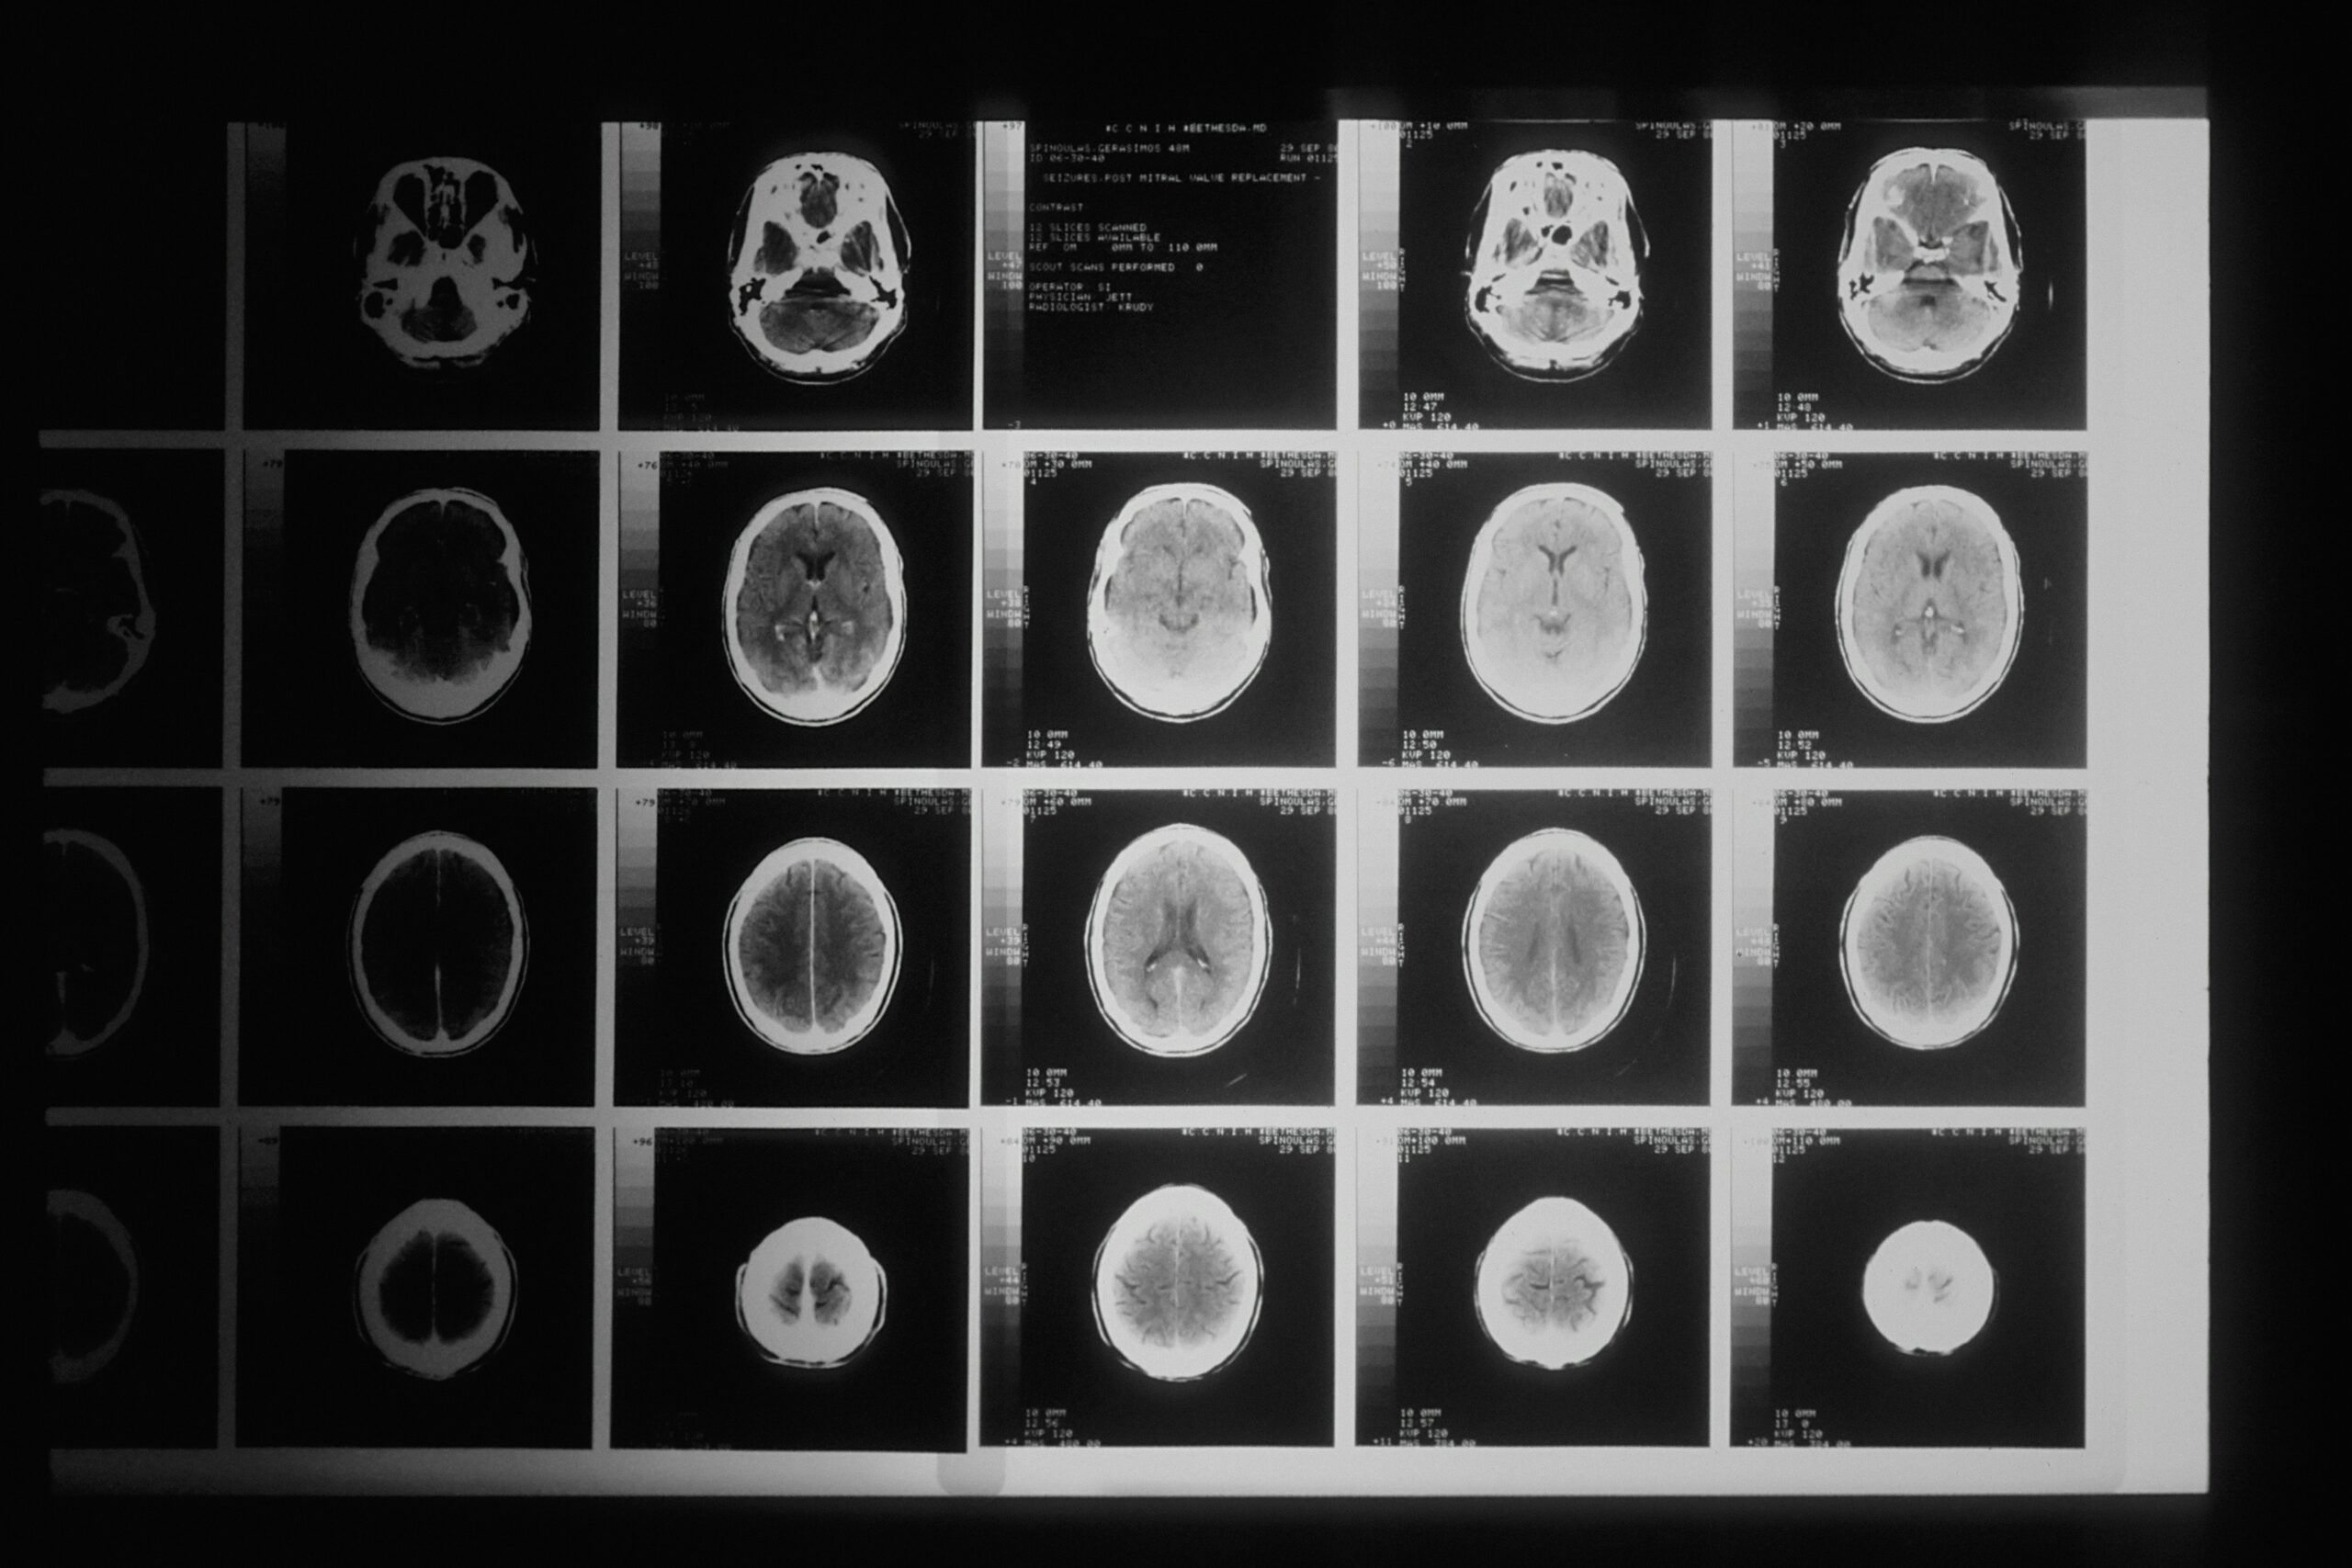

Median tuottama ymmärrys aivoista on sosiaalisesti ja kulttuurisesti välittynyttä. Jo aivoja koskeva tieteellinen tieto muodostuu aivojen, aivokuvantamisteknologioiden sekä dataa tulkitsevien tutkijoiden yhteistyössä. Median tutkijahaastatteluissa ja aivotreenivinkeissä tietoa sovelletaan monimutkaisiin yhteiskunnallisiin ilmiöihin.